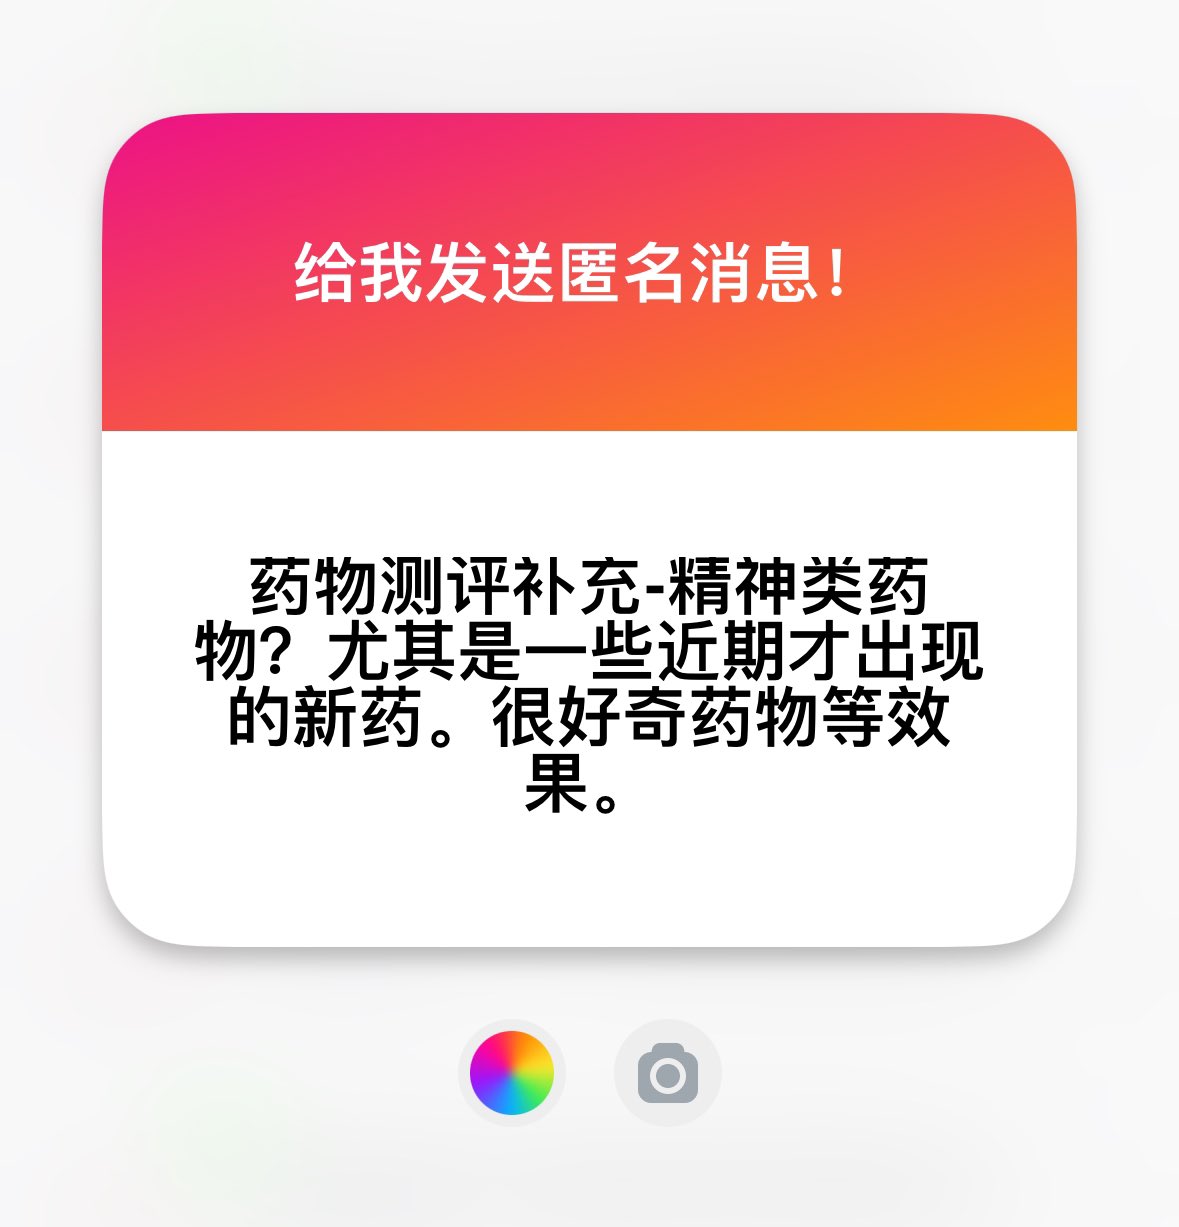

关于后藤提到过的“反解离”

首先,从定义上讲,“反解离(anti-dissociative)”并不是一个标准的医学术语或者广泛认同的药理学分类。在正规资料,比如医学文献、维基百科、精神药理学教科书中,目前并没有“反解离药物”这个正式概念。

看上去像是为了描述某类特定效应而创造的术语(可能是nmda受体活性增强),用来对抗因NMDA受体拮抗剂(比如氯胺酮、DXM、PCP等)引发的解离体验(dissociation)。

那么更常见的是将其归入认知增强剂(cognitive enhancers),特别是改善认知连接性(connectivity)和现实感知(reality testing)的类型。

关于后藤提到过的“反解离”

首先,从定义上讲,“反解离(anti-dissociative)”并不是一个标准的医学术语或者广泛认同的药理学分类。在正规资料,比如医学文献、维基百科、精神药理学教科书中,目前并没有“反解离药物”这个正式概念。

看上去像是为了描述某类特定效应而创造的术语(可能是nmda受体活性增强),用来对抗因NMDA受体拮抗剂(比如氯胺酮、DXM、PCP等)引发的解离体验(dissociation)。

那么更常见的是将其归入认知增强剂(cognitive enhancers),特别是改善认知连接性(connectivity)和现实感知(reality testing)的类型。